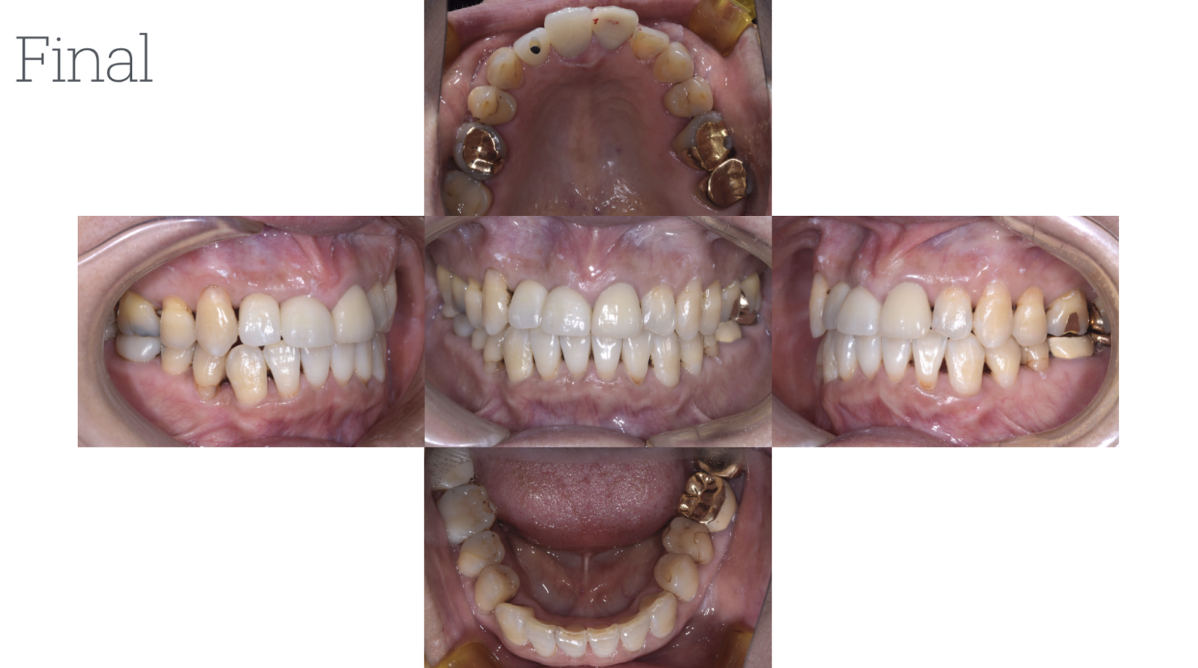

患者3

年齢性別:60代女性

主訴:以前より、見た目の改善を含め、奥歯の摩耗が気になっており治療を希望。

まずは、矯正治療にて歯のポジションを改善。その後、インプラントと金属の除去にて回見合わせを最終調整。全体的な噛み合わせが改善し、歯軋りも気にならなくなったとのこと。現在、定期検診を継続中。